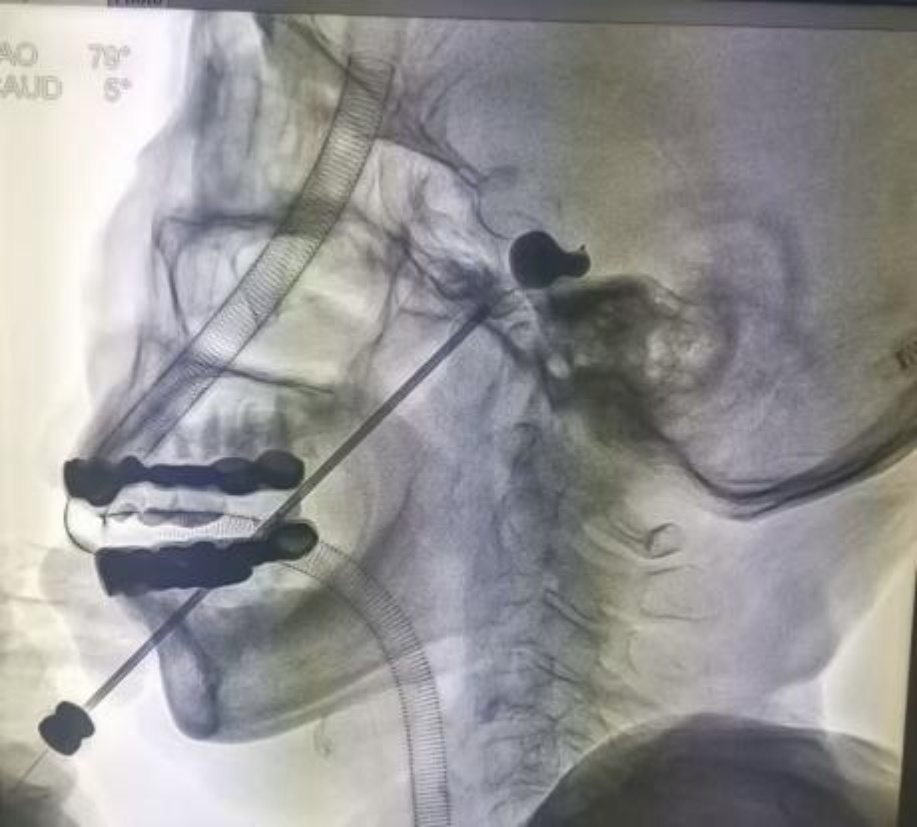

本研究中的压力维持策略要求术中动态调控,为补偿因组织顺应性所致的压力衰减,维持初压组患者术中追加的造影剂量约为0.05~0.15 mL。这一微量追加旨在精确维持力学环境,而非显著改变球囊容积。相关研究指出[13],当球囊置于Meckel腔内充盈后,其最终形态主要受Meckel腔本身以及三叉神经孔的解剖形态所制约,若囊内压力过高,球囊可能因过度扩张而呈现“类球形”,或部分经三叉神经孔疝入后颅窝而形成“哑铃形”。值得注意的是,本研究中维持初压组尽管在压力维持期间追加了微量造影剂,动态影像监测(图1)显示球囊形态虽随压力维持略有扩张,但仍保持典型的“梨形”,未出现向上述异常形态的显著转变,如图2所示。我们认为,这一结果可能源于本研究设定的压力维持范围(初压的±5%)所对应的压力与容积增量,尚未达到使Meckel腔硬膜壁发生塑性变形或球囊明显向后颅窝溢出的生物力学阈值。Meckel腔作为硬膜构成的纤维性腔隙,其周壁及相邻的岩骨嵴等骨性结构形成了有效的解剖约束,在本研究参数下足以将球囊限制于腔内,从而维持其理想的“梨形”形态。

(A) 首次达到标准梨形 (B) 手术结束时

Figure 2. Intraoperative balloon morphology

2. 术中球囊形态